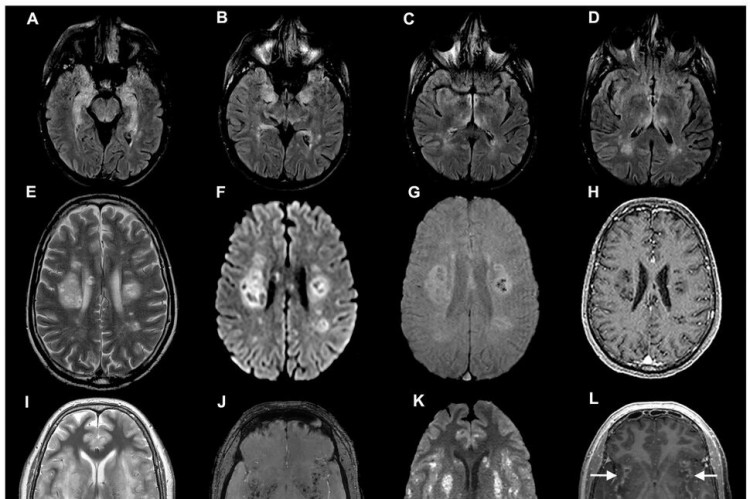

Além de ser uma doença respiratória, a Covid-19 também afeta o cérebro humano, provocando manifestações como delírios e perda de olfato e/ou paladar. Não é de se estranhar: evidências já demonstravam que os coronavírus Sars-Cov (2002) e Mers (2012) também infectavam o cérebro, induzindo a encefalites, encefalopatia e Acidentes Vasculares Cerebrais (AVCs). O apresentador do SportTV, Rodrigo Rodrigues morreu, em julho, vítima de complicações neurológicas após a Covid-19.

No entanto, o Sars-Cov-2, vírus causador da Covid-19, parece ter mais efetividade ao alcançar o sistema nervoso. Isso faz com que ele provoque manifestações mais intensas em comparação aos outros coronavírus. Assim, estima-se que cerca de 40% das pessoas contaminadas com o novo coronavírus apresentam sintomas neurológicos.

Uma certeza é de que a Covid-19 ataca os neurônios, como indicado por pesquisa da Universidade de Yale, ainda em preprint (que ainda precisa de revisão de outros pesquisadores) e publicada dia 8 de setembro de 2020.

A pesquisa demonstrou que o vírus atinge principalmente o córtex, a parte mais superficial do cérebro. De acordo com as observações, o Sars-Cov-2 não destrói as células infectadas, mas parece suprimir a comunicação com outras células e “sugar” o oxigênio delas, provocando a morte da região ao redor do organismo.

“É muito preocupante que o Sars-Cov-2 infecte neurônios do córtex cerebral. Ainda mais preocupante é que não se encontrou no tecido cerebral grande infiltrado imune, sugerindo que a resposta imune pode ser inadequada no cérebro”, analisa o neurocientista. Segundo ele, ainda há muito a se estudar sobre a resposta imunológica do corpo humano à Covid-19 no órgão.